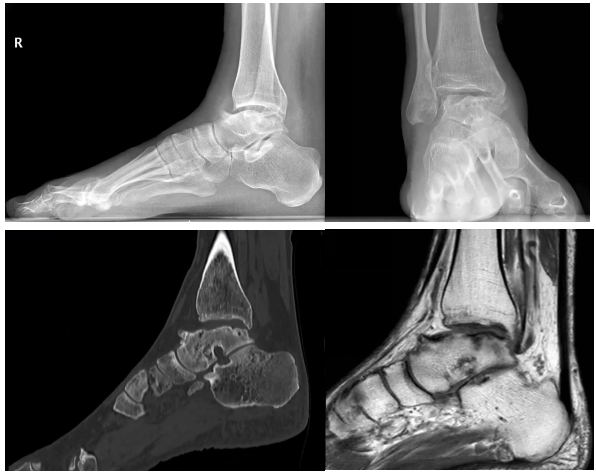

患者张某,男,50岁,因“反复性右踝关节疼痛7年,加重1年伴活动受限”入院,主诉右踝反复性疼痛、肿胀,严重影响日常活动,期间多次往返上级医院就诊、咨询,诊断为右踝关节炎终末期,建议行开放式踝关节融合手术治疗,但考虑到手术创伤大,恢复时间长,患者一直犹豫不决,经咨询,得知临汾市人民医院可开展踝关节镜微创技术,遂来我院手术治疗。

术前

我院治疗团队采用了关节镜辅助下踝关节融合术进行治疗,关节镜下发现踝关节面软骨破坏严重,彻底清理了关节内的滑膜组织及软骨,经皮三枚空心钉加压固定加压效果良好,操作微创,术后患者恢复良好,实现了骨性融合,无切口并发症出现,疼痛症状明显减轻,行走活动能力较术前改善,患者对于治疗效果感到满意。